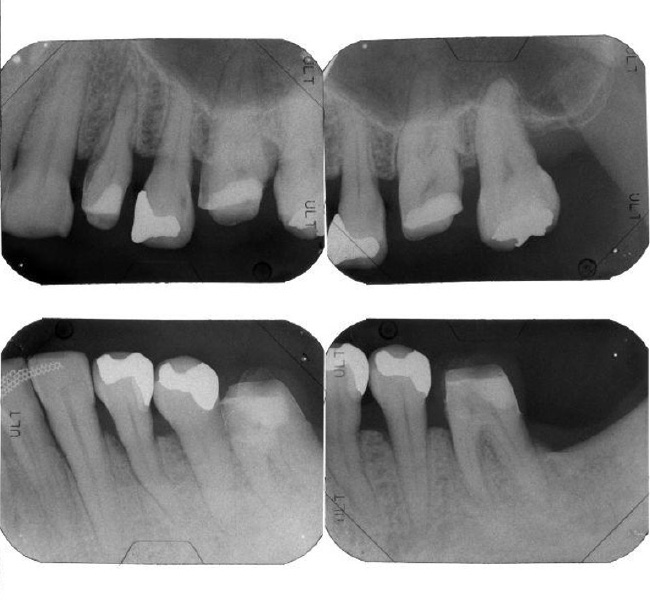

治療前

| 治療内容 | 全顎治療:歯周病治療、抜歯、根管治療、 咬合治療・矯正治療、フルメタルクラウン(保険) |